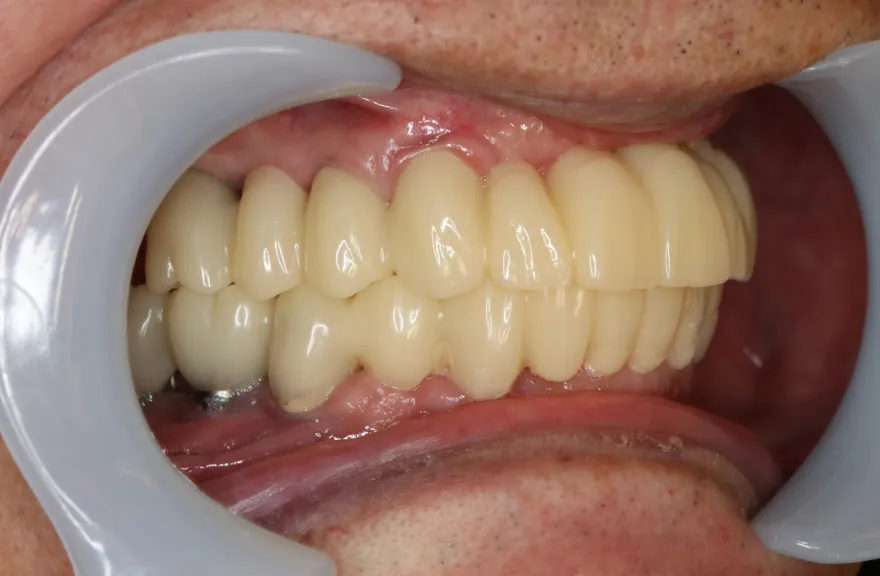

年齢を考えると、今回の治療で歯科治療を終えてしまい、残りの人生においてはメンテナンスのみで歯科へ通う状況を作りきってしまうことが求められました。

以上より、潔く残っている歯牙は抜去させていただき、上下をインプラントフィクスチャーによって固定式の歯を入れることとしました。 - 治療のリスク

複数のインプラントフィクスチャーの埋入においては埋入位置がずれると後々のクラウン製作に難が生じます。そのリスクを最低限にするため、ガイデッドサージェリーを行っております。